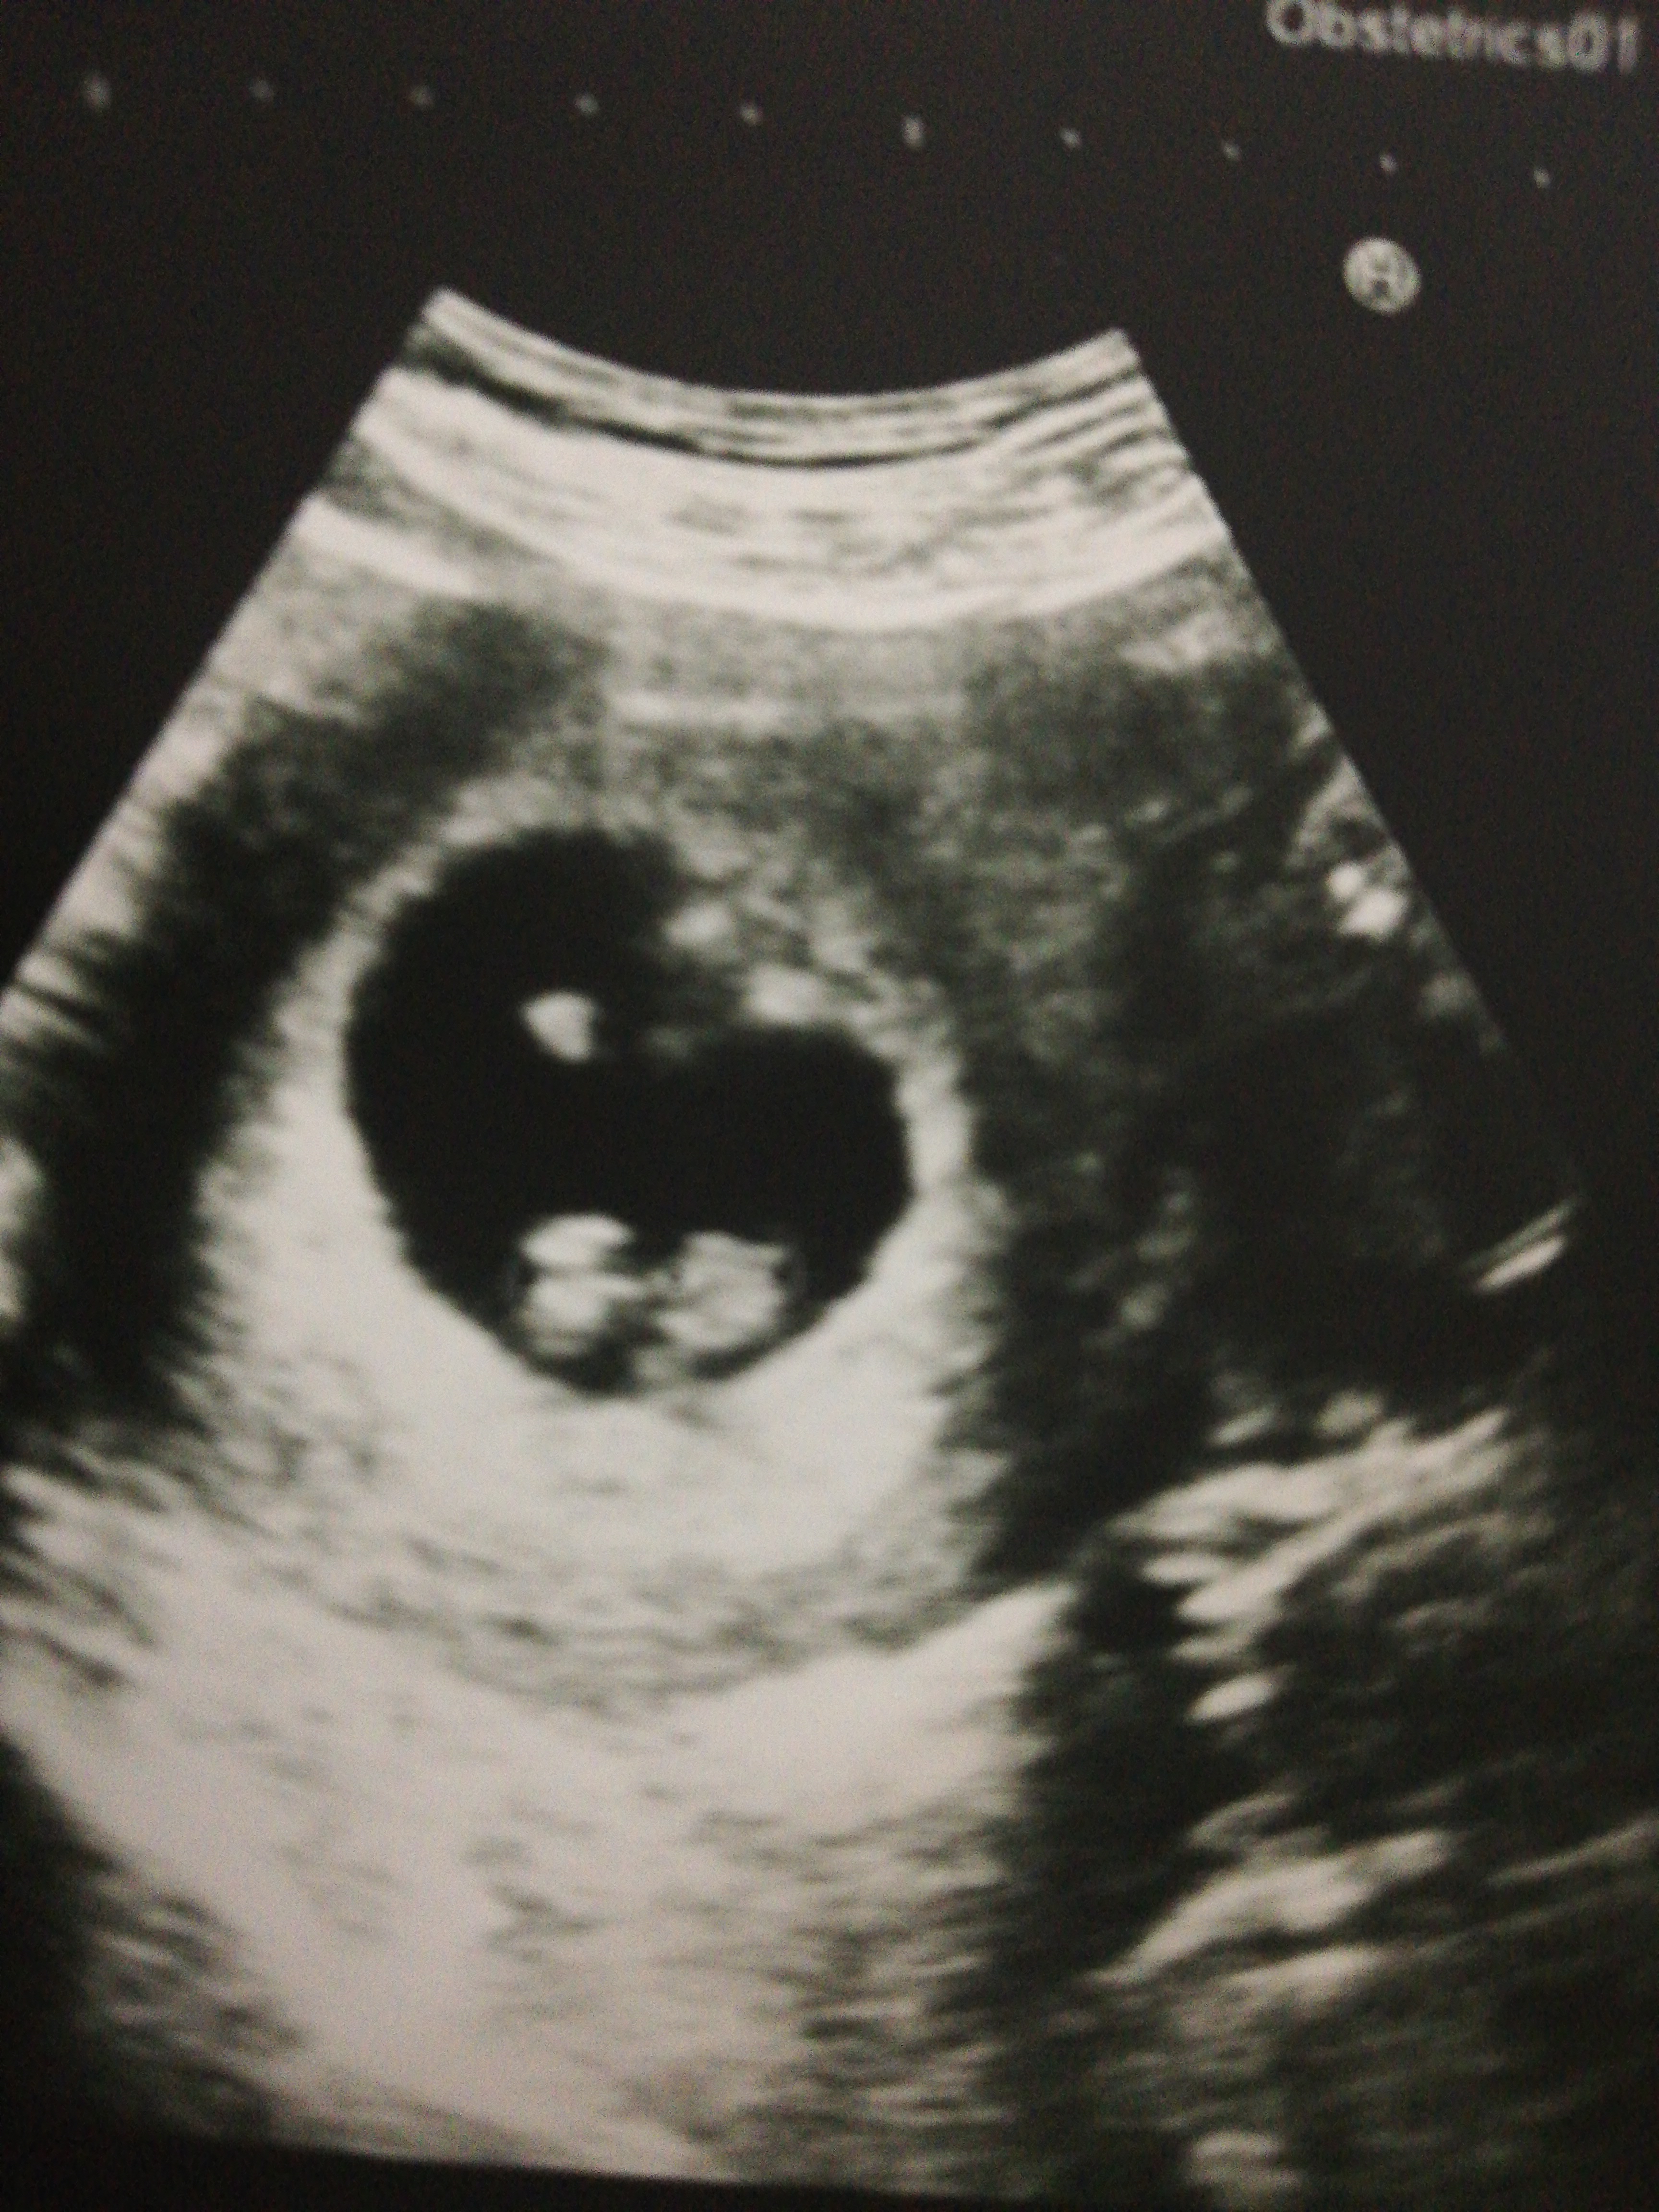

Cinsiyet tahmini merek ediyorum erken ama

Konu Başlığı Cinsiyet tahmini merek ediyorum erken ama

Selam 15 haftalikdi 2 ci gebeliyimdi cok farkli geciriyorum hic bulanti yox normaldi hersey ama kizimda hep bulanti kotu olurdum ama buda kiz dedi doktor. tahminimde erkek idi